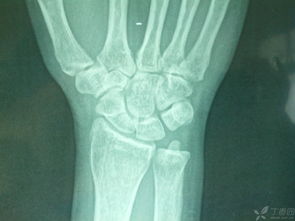

看了你追加描述和图片,基本确定是骨折!不打算去医院的话就按照我上面说的做,狠狠心找到骨折的地方,试着做一下整复,外边用硬纸壳固定!可以去买一些人药!狗狗会很快好起来的

根据外伤史和局部症状可以确诊,必要时对宠物宝贝进行X射线检查或照相。